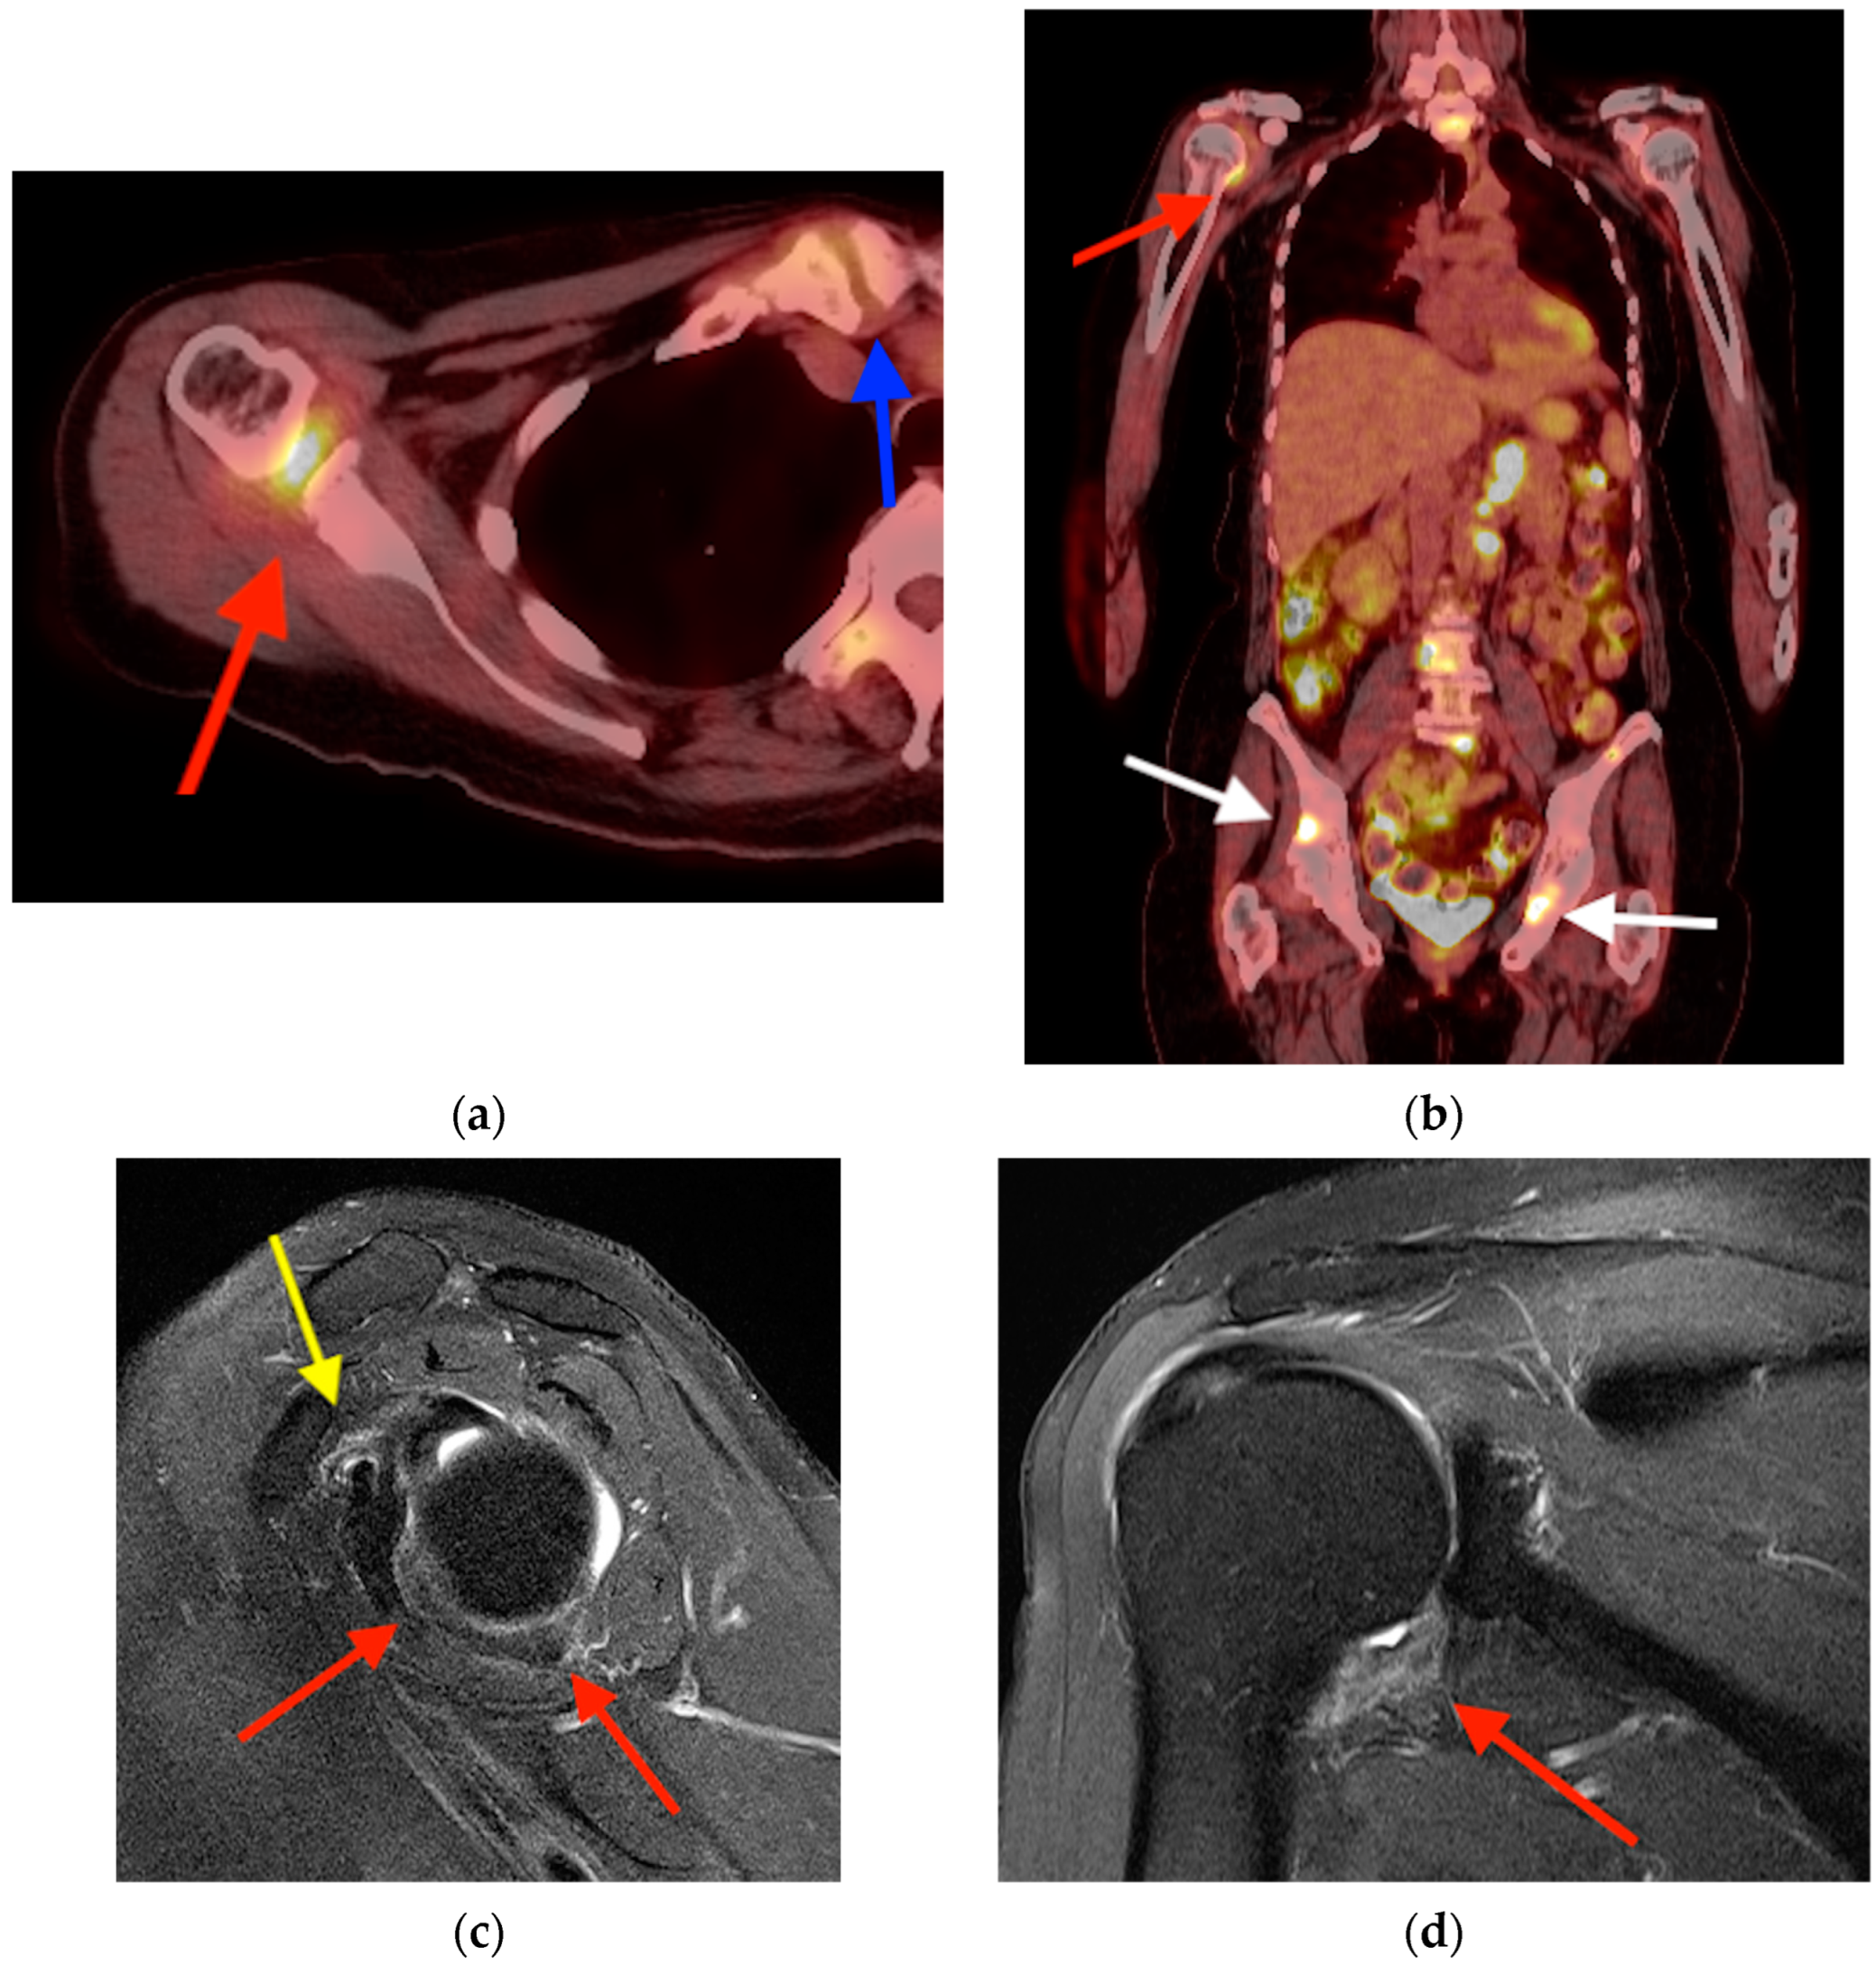

4.2. Adhesive Capsulitis

- Neviaser, A.S.; Neviaser, R.J. Adhesive capsulitis of the shoulder. J. Am. Acad. Orthop. Surg. 2011, 19, 536–542. [Google Scholar] [CrossRef] [PubMed]

- Waldburger, M.; Meier, J.L.; Gobelet, C. The frozen shoulder: Diagnosis and treatment. Prospective study of 50 cases of adhesive capsulitis. Clin. Rheumatol. 1992, 11, 364–368. [Google Scholar] [CrossRef] [PubMed]

- Sridharan, R.; Engle, M.P.; Garg, N.; Wei, W.; Amini, B. Focal uptake at the rotator interval or inferior capsule of shoulder on 18F-FDG PET/CT is associated with adhesive capsulitis. Skelet. Radiol. 2017, 46, 533–538. [Google Scholar] [CrossRef] [PubMed]

- Fields, B.K.; Skalski, M.R.; Patel, D.B.; White, E.A.; Tomasian, A.; Gross, J.S.; Matcuk, G.R. Adhesive capsulitis: Review of imaging findings, pathophysiology, clinical presentation, and treatment options. Skelet. Radiol. 2019, 48, 1171–1184. [Google Scholar] [CrossRef]